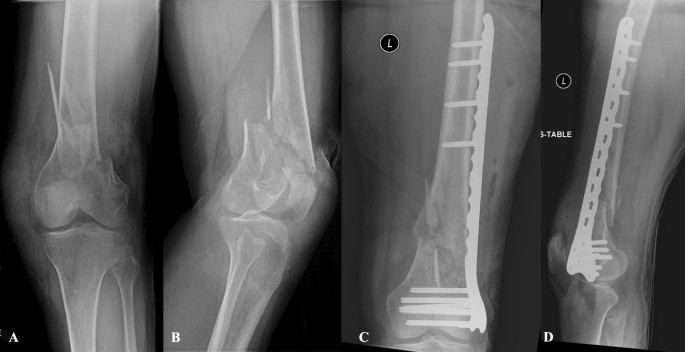

- Tibia and fibula fractures – injuries to the shinbone and outer leg bone, ranging from simple to complex fractures.

- Open reduction and internal fixation (ORIF) – using metal plates, screws, or rods to stabilise broken bones.